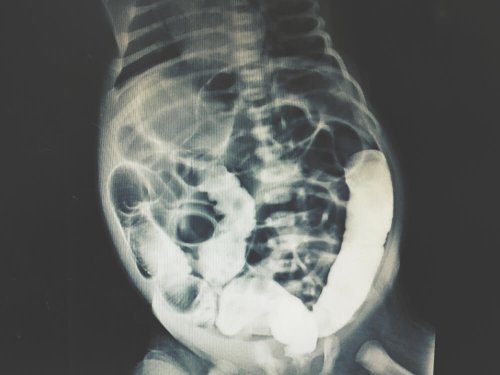

Como as evidências científicas indicam, atualmente é um exame médico altamente confiável que produz uma quantidade mínima de falsos positivos ou outros erros. Além disso, é usado em conjunto com outros diagnósticos médicos por imagem. É o caso da tomografia axial computadorizada (TAC) ou da ressonância magnética (RM).

De acordo com os resultados obtidos, o grupo de especialistas pode determinar a causa da alteração abdominal. Também podem ser realizados exames de imagens internas da região abdominal para facilitar o diagnóstico.